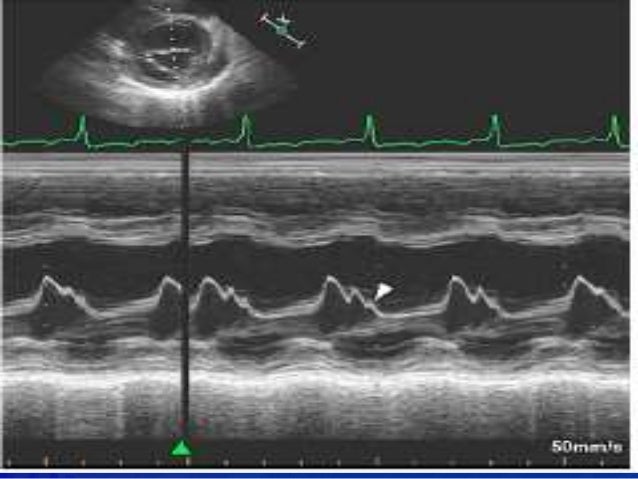

Mitral Stenosis Echocardiography - Wikidoc

Mitral stenosis echocardiography - wikidoc www.wikidoc.org

mitral stenosis mode echocardiography echo wikidoc findings